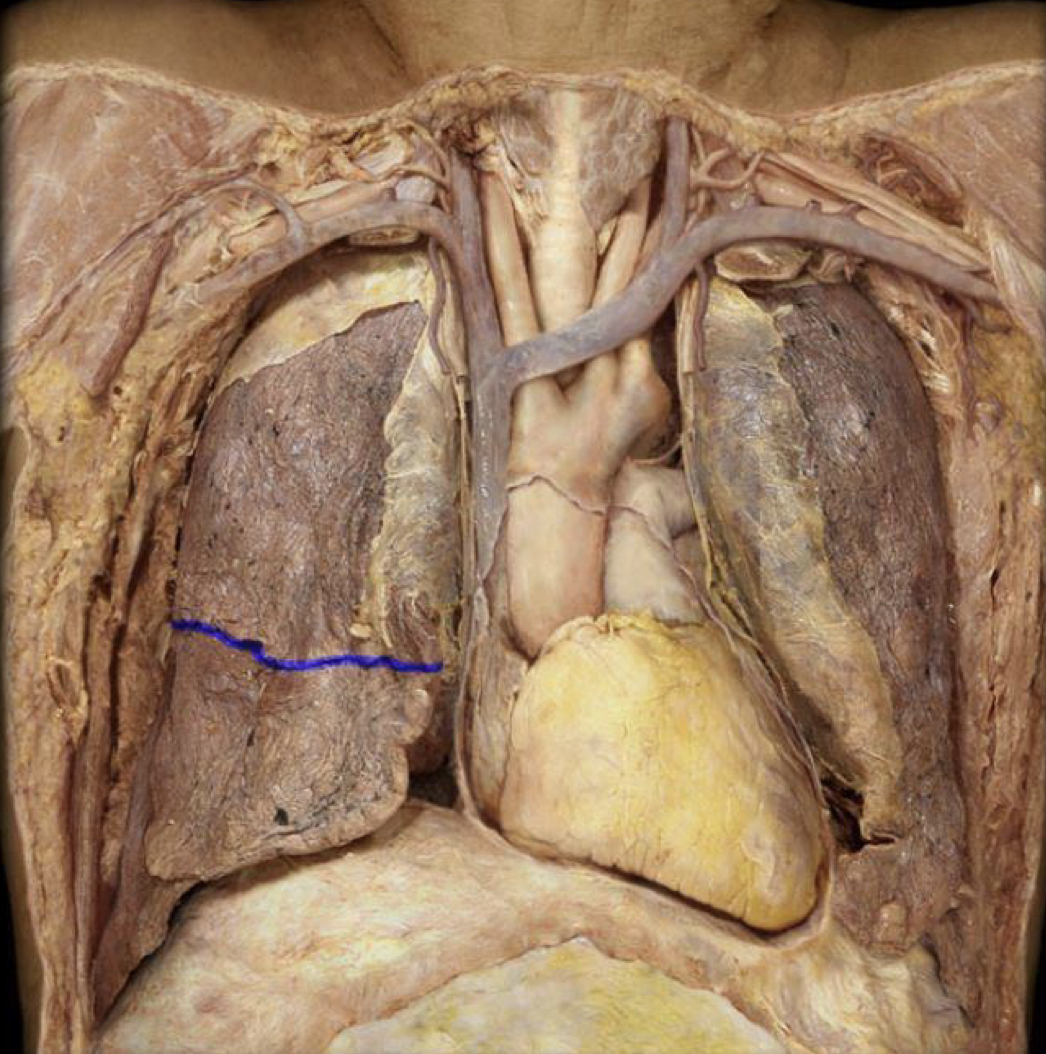

What structure is highlighted in blue?

Horizontal fissure of Right lung